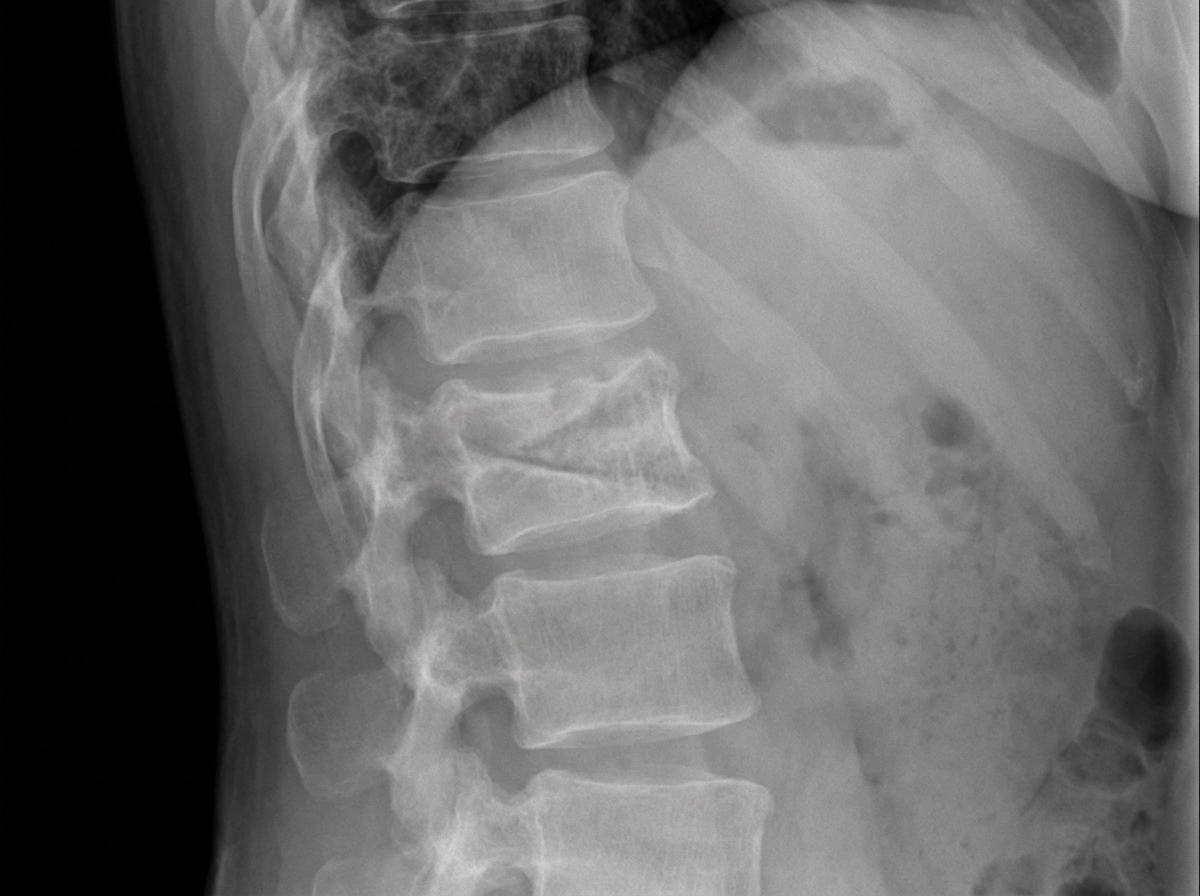

The following X-ray shows a 13-year-old child presenting with difficulty in breathing and gradually developing respiratory compromise. What is the diagnosis?

Explanation: ***Kyphoscoliosis*** - **Severe spinal curvature** in both sagittal (kyphosis) and coronal (scoliosis) planes causes **thoracic cage deformity**, restricting lung expansion and causing respiratory compromise. - X-ray shows **combined anterior angulation and lateral curvature** of the spine, leading to reduced **pulmonary function** and **restrictive lung disease**. *Lordosis* - **Excessive inward curvature** of the lumbar spine does not typically cause **respiratory compromise** or breathing difficulties. - Primarily affects **lower back posture** and does not significantly impact **thoracic cavity** dimensions or lung function. *Scheuermann's Disease* - Characterized by **wedge-shaped vertebrae** causing thoracic kyphosis, but typically **mild to moderate** and rarely causes severe respiratory compromise. - Usually presents with **back pain** and **postural changes** rather than acute breathing difficulties in adolescents. *Koch's Spine* - **Tuberculous spondylitis** presents with **vertebral destruction**, **abscess formation**, and **neurological deficits** rather than primary respiratory symptoms. - X-ray would show **vertebral collapse**, **disc space narrowing**, and possible **paravertebral abscess**, not the characteristic curved deformity causing thoracic restriction.